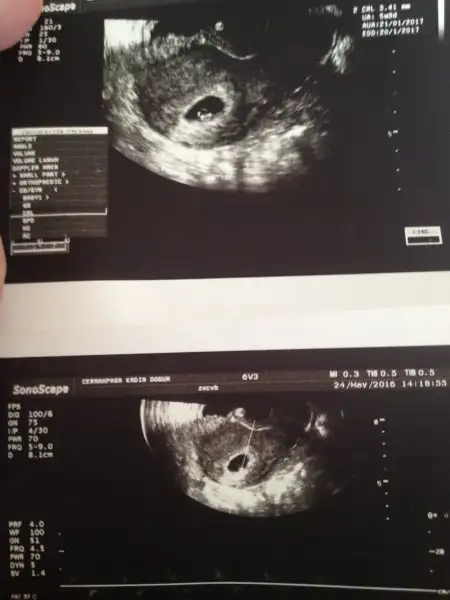

6. Hafta , 7. Hafta (ikisi de vaginal) ve 11+5 haftalık usg